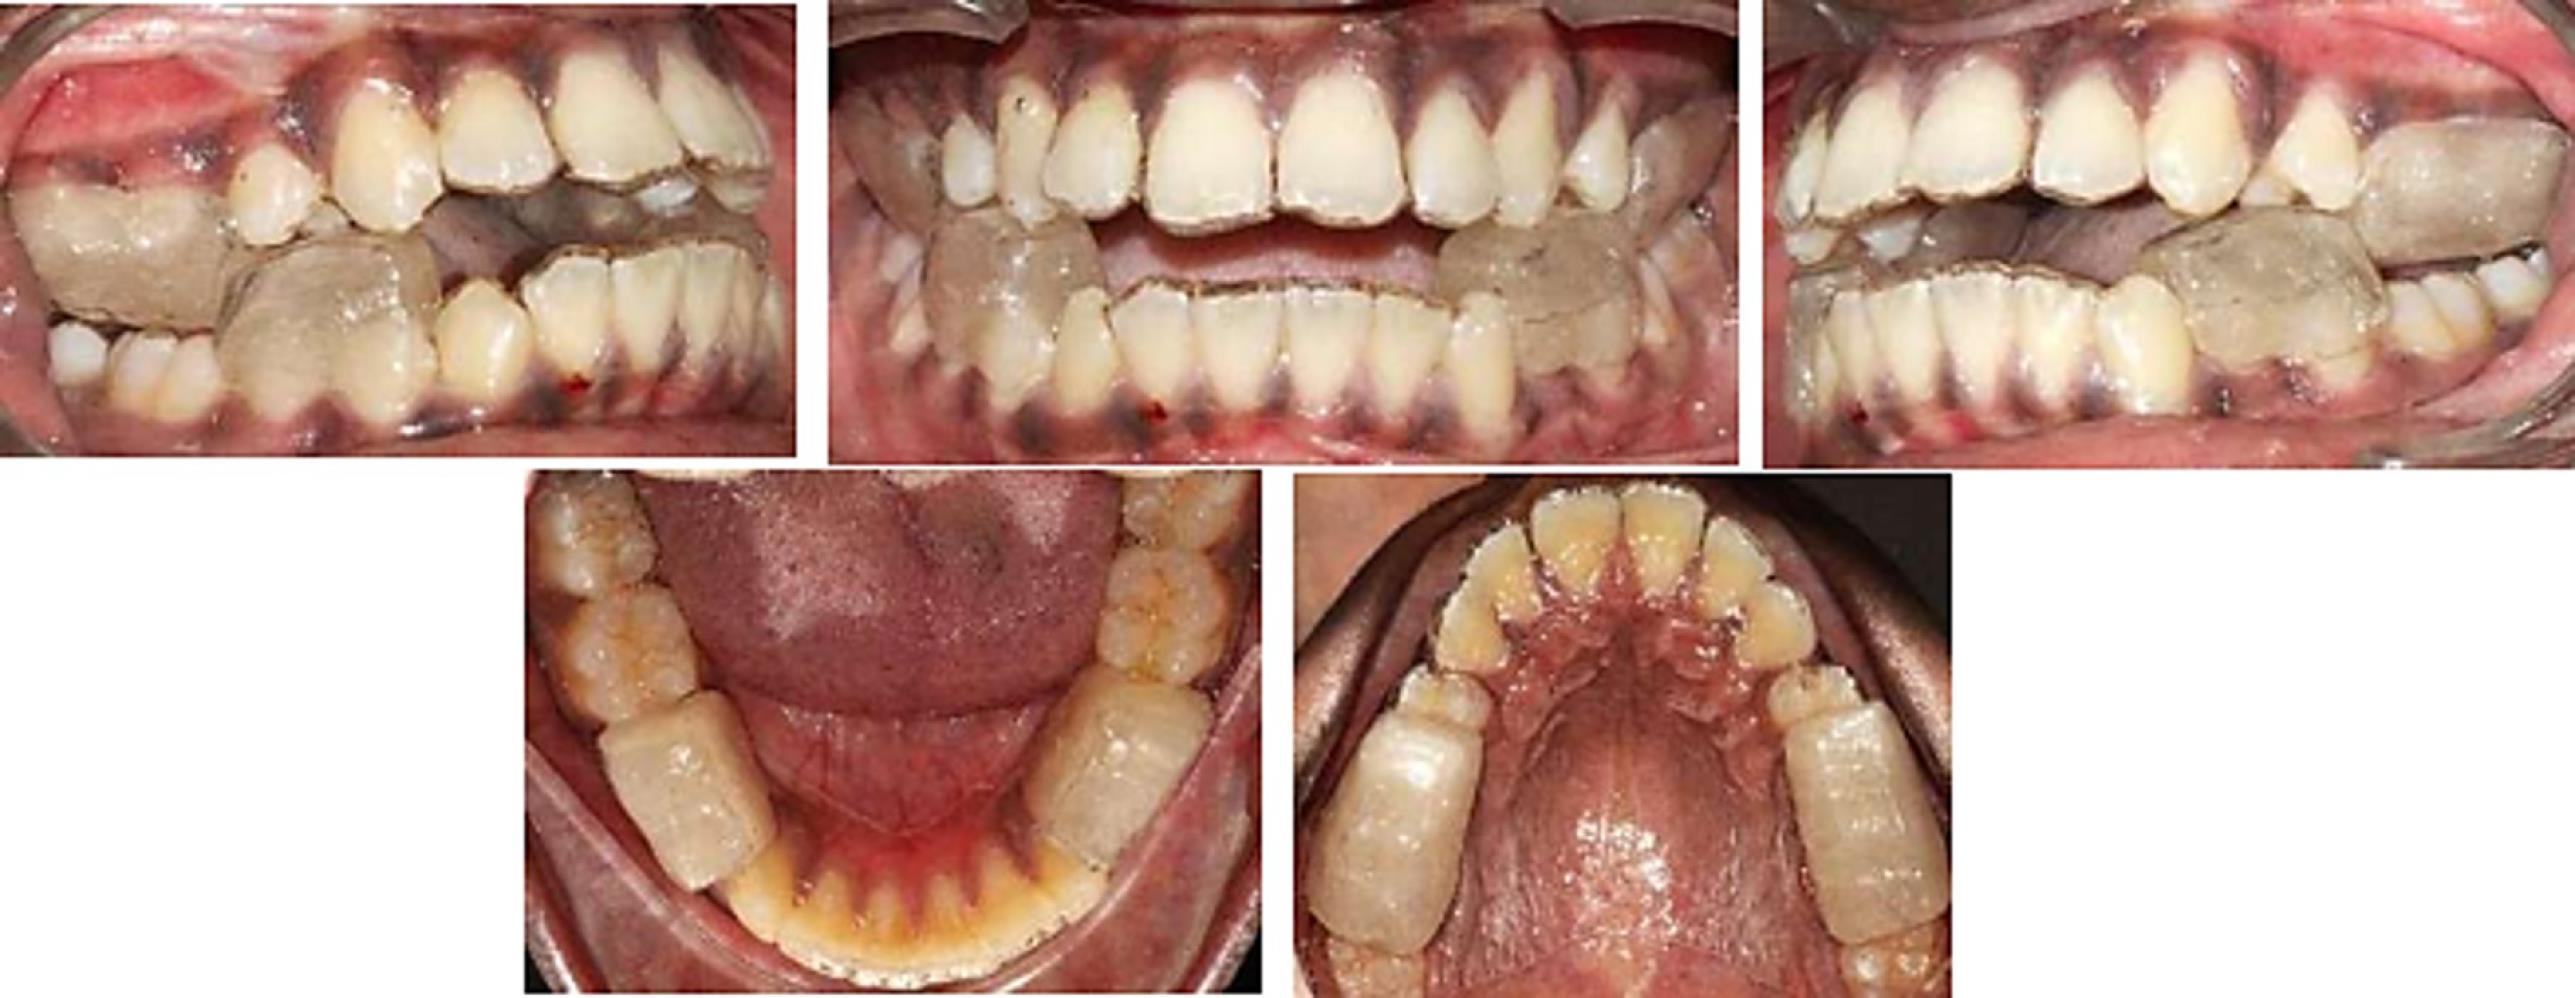

Figure 3 depicts the preoperative extraoral and intraoral status of patients.

Figure 3.

Patient’s intraoral and extraoral pre-treatment photographs of clear functional jaw corrector appliance (CFJC) (the test group)